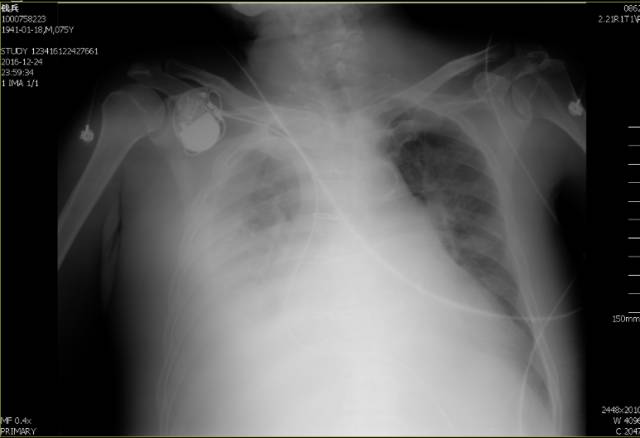

胸片

诊断

1、慢性心力衰竭(全心衰,右心衰为主)

2、重度肺动脉高压

2、病态窦房结综合征 心房颤动 单腔起搏器植入术后

3、心脏瓣膜病 二尖瓣+主动脉瓣机械瓣置换术后

4、2型糖尿病

5、高血压病3级 极高危组

6、肾功能不全

T:36.5℃,R:18次/分,P:65次/分,BP:140/70mmHg,神清,慢性病容,半卧位,颈软,颈静脉怒张,双肺呼吸音清晰,双下肺呼吸音减低,双下肺可闻及湿性罗音,心律齐,可闻及机械瓣音,未闻及杂音。腹膨隆,质软,无压痛及反跳痛,肝脾肋下未触及,移动浊音阳性,双下肢中度水肿。骶尾部可见0.5*0.5cm皮肤破溃已结痂,及5*6cm压红,压之不褪色。 \u000b